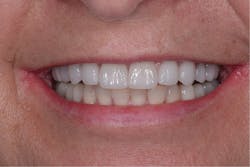

Figure 7: Anterior retracted view of the patient’s final restoration

Figure 8: Anterior smile view of the patient’s final restoration